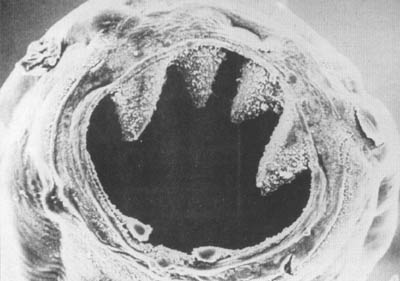

En muchas partes del mundo, donde predomina la anemia por carencia de hierro, se debe tanto a pérdidas de hierro como a pobre consumo de éste. Siempre que el organismo pierde sangre, también pierde hierro. Por lo tanto, se pierde hierro con la menstruación y en el parto, y además cuando existen estados patológicos como úlcera péptica sangrante, heridas y una variedad de entidades clínicas que implican pérdida de sangre ya sea por sistema intestinal o urinario, la piel o diversas superficies en las mucosas. Indudablemente una de las causas más notorias e importantes de pérdida sanguínea es la uncinaria (Foto 20), parásito que puede estar presente en grandes cantidades. Estos gusanos chupan sangre, dañan la pared intestinal, y causan pérdida de sangre. Unos 800 millones de personas en el mundo están infestadas con uncinaria. Otros parásitos intestinales como el Trichuris trichiura pueden también contribuir a la anemia. Los esquistosomas o bilharzias, que son de varios tipos, ocasionan asimismo pérdida de sangre ya sea en el tracto genitourinario (en el caso del Schistosoma haematobium) o en el intestinal. La malaria, otra infección parasitaria muy importante destruye los eritrocitos parasitados, y puede llevar a la anemia hemolítica, en vez de anemia por carencia de hierro. En los programas para aminorar la anemia se pueden requerir acciones para el control de las infecciones parasitarias y reducir la pérdida sanguínea que resulta de la enfermedad, lo mismo que mejorar el consumo de hierro alimentario.

FOTO 20

Las fauces de una uncinaria; estos parásitos causan pérdida de

sangre y de hierro en los intestinos y son causa importante de anemia